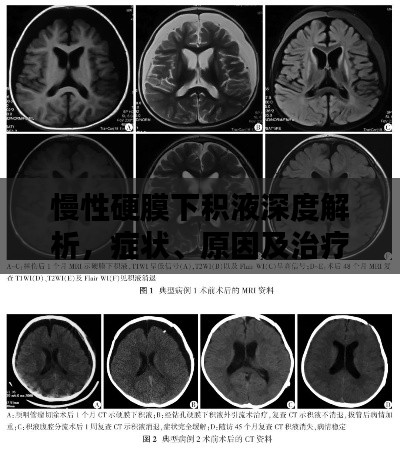

对于慢性硬膜下积液的诊断,通常需要进行头颅CT或MRI等影像学检查,治疗方法主要包括药物治疗和手术治疗,药物治疗主要是对症治疗,如使用脱水药物降低颅内压等,对于严重的慢性硬膜下积液,可能需要手术治疗以消除积液并恢复颅内压力平衡。